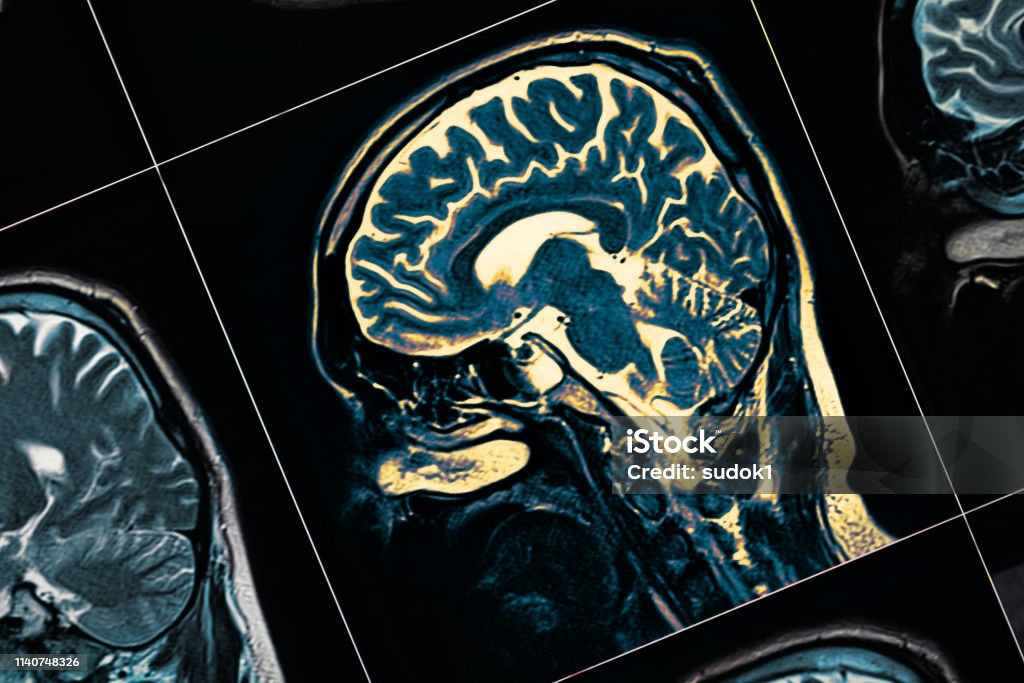

Las redes cerebrales son como caminos por los que las distintas partes del cerebro se comunican entre sí. Gracias a estas conexiones, podemos movernos, pensar y sentir con normalidad. En la enfermedad de Parkinson, estas redes no funcionan bien. Los científicos han descubierto que algunas zonas del cerebro están demasiado conectadas entre sí, lo que se llama hiperconectividad. Esto puede alterar el control del movimiento y provocar síntomas como temblores, rigidez o lentitud. Estos nuevos descubrimientos son importantes porque ayudan a entender el Parkinson no solo como un problema de una parte del cerebro, sino como un problema de comunicación entre varias áreas. En el futuro, este conocimiento podría ayudar a crear mejores diagnósticos y tratamientos más efectivos.